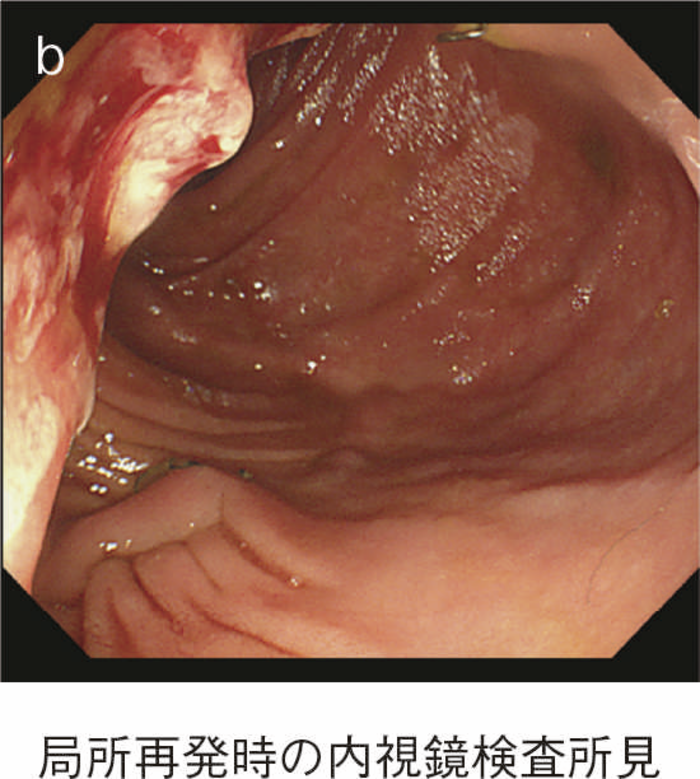

直腸粘膜をすべて切除し,回腸囊と肛門を手縫い吻合する。UCに対しても根治性が高い術式である。図14のように,肛門管粘膜の切除開始ラインは歯状線の肛門側で,肛門陰窩をすべて切除する。切除開始ラインが歯状線よりも口側になり,一部肛門管粘膜(移行帯上皮)を温存させた結果,この残存した粘膜からの発癌を強く示唆する症例報告も存在する2)。また,IAAを行ったにもかかわらず,術後に発癌したという症例報告も存在するが,多くは術後3年以内に発症している症例が多く,術前の直腸癌の局所再発が原因ではないかとの意見が一般的である3)。下部直腸から肛門管にかけて早期癌を合併するような症例では,術後の病理検査で,DM0,RM0であっても図15のように局所再発を生じる可能性もあるので,定期的な画像診断とともに,直腸診を行い,局所再発がないことを確認すべきである4)。

図15 IAA後に局所再発を生じた症例

UC術後の回腸囊には回腸囊炎を合併する症例があることは広く知られており,本邦においても増加傾向である。UC術後のpouchからの腫瘍の発症率は術後10年で1.3%,20年で4.2%との報告がある8)。また,術前に癌を合併していた症例は,回腸囊の発癌のrisk factorであると報告されている8)。そのため癌/dysplasiaで手術となった症例や難治性の回腸囊炎を合併した症例では回腸囊のサーベイランスも必要となる。図19に回腸囊炎を繰り返し,術後30年目に回腸囊内にHGDを合併し回腸囊切除を行った症例の内視鏡検査所見を示す9)。

図19 回腸囊内にHGDを合併した症例